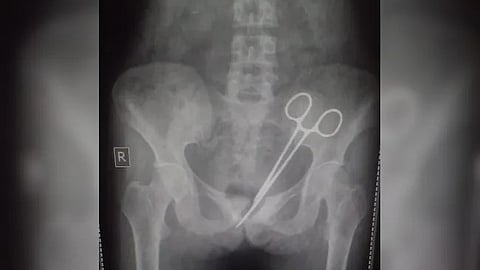

സിക്കിമിലെ ഗാങ്ടോക്കിൽ അപ്പെൻഡിക്സ് സർജറി നടത്തിയ 45 കാരിയായ യുവതിയുടെ വയറ്റിൽ നിന്നും 12 വർഷത്തിനു ശേഷം സർജിക്കൽ കത്രിക കണ്ടെത്തി ഡോക്ടമാർ. 2012 ൽ അപ്പെൻഡിക്സ് ശസ്ത്രക്രിയ നടത്തിയ ശേഷമാണ് യുവതിക്ക് വയറുവേദന സ്ഥിരമായത്. തുടർന്ന് ഒട്ടേറെ ഡോക്ടർമാരെ കാണിച്ചെങ്കിലും ആർക്കും വയറുവേദനയുടെ കാരണം കണ്ടെത്താനായില്ല. ഒടുവിൽ കഴിഞ്ഞ മാസം നടത്തിയ പരിശോധനയിലാണ് യുവതിയുടെ വയറ്റിൽ 12 വർഷങ്ങൾക്ക് മുമ്പ് കത്രിക മറന്നു വെച്ചതായി കണ്ടെത്തിയത്.

കഴിഞ്ഞ ഒക്ടോബർ 8 ന്, വീണ്ടും എസ്റ്റിഎൻഎം ആശുപത്രിയിൽ പോയി നടത്തിയ എക്സ്-റേയിലാണ് വയറ്റിലെ ശസ്ത്രക്രിയ കത്രിക കണ്ടെത്തിയത്. കത്രിക നീക്കം ചെയ്യുന്നതിനായി മെഡിക്കൽ വിദഗ്ധരുടെ ഒരു സംഘം ഉടൻ തന്നെ ശസ്ത്രക്രിയ നടത്തി കത്രിക പുറത്തെടുക്കുകയും യുവതി സുഖം പ്രാപിക്കുകയും ചെയ്തു. സംഭവത്തിൽ അന്വേഷണം ആരംഭിച്ചു.